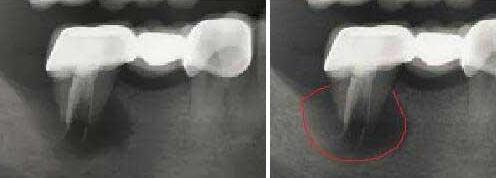

深圳牙科醫生表示,拍牙片不是為(wei) 了了解牙齒本來的情況,比如說牙根有沒有囊腫,以及是否有牙槽骨吸收,是否有多生牙,智齒,等情況,牙片是醫生診斷牙齒病情的主要依據,可以提高牙科治療的準確性,所以拍牙片是有必要的。